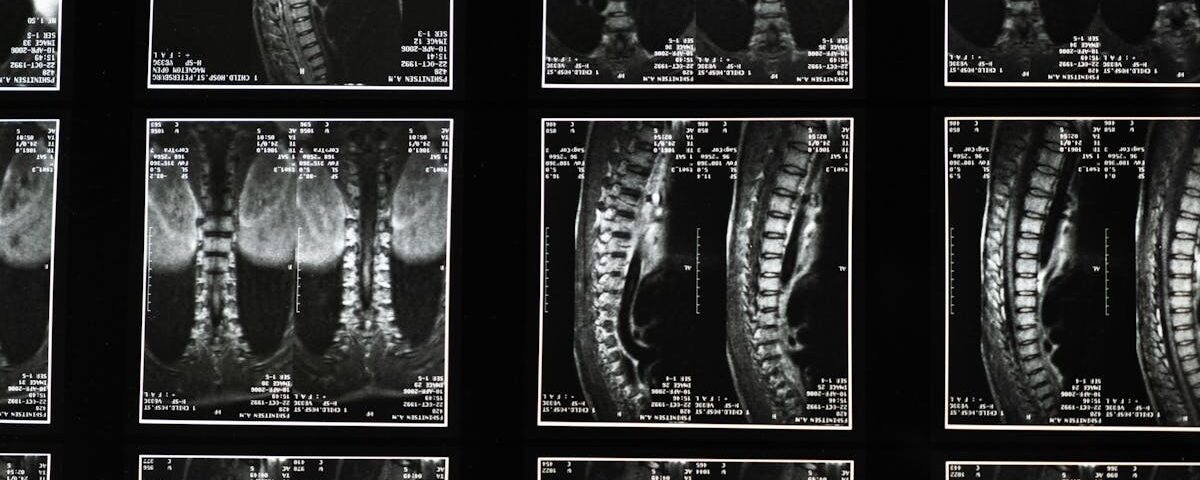

La sciatique résulte souvent de la compression ou de l’irritation du nerf sciatique. Cela peut être engendré par divers facteurs, notamment des hernies discales, une sténose spinale, ou encore des problèmes musculaires. La douleur, qui peut varier de légère à intense, peut impacter significativement la qualité de vie des personnes atteintes.

La sciatique se manifeste par une douleur intense qui irradie du bas du dos aux fesses, puis le long de l’arrière de la jambe. Cette douleur peut être causée par divers facteurs, notamment une hernie discale, une arthrose ou tout simplement une compression du nerf sciatique, résultant de mouvements brusques ou de mauvaises postures.

L’impact du surpoids sur la douleur sciatique

Le surpoids a des effets significatifs sur la mécanique du corps, et cela se traduit dans le cas de la sciatique. En effet, l’excès de poids génère une pression supplémentaire sur la colonne vertébrale et les articulations. Cet excès de tension peut compromettre l’intégrité des disques intervertébraux, augmentant le risque de hernie discale et de stenose spinale, des conditions qui sont souvent à l’origine de douleurs sciatiques.